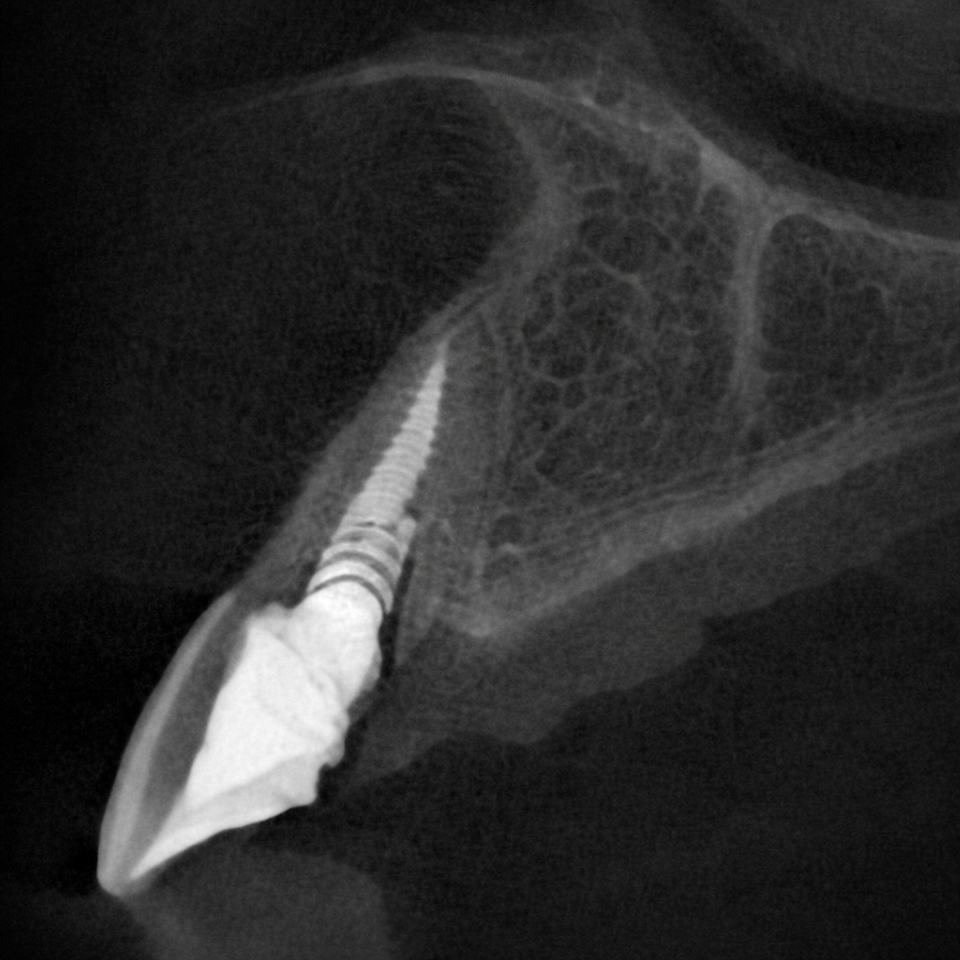

At our practice, we recently helped a patient restore their smile after experiencing a complex dental issue involving a periodontal infection and a root fracture. To fully restore both health and aesthetics, we recommended a comprehensive implant-based solution.

The treatment process included:

• Extraction and Bone Grafting to properly prepare the site for implant placement

• Implant Placement with Soft Tissue Grafting to ensure long-term stability and natural-looking gum contours

• Provisional Implant-Supported Crown to maintain appearance and function during healing

• Final Implant-Supported Crown, custom-designed for strength, beauty, and seamless integration

We are extremely proud of the final result, and most importantly, our patient is now enjoying a healthy, confident smile once again.